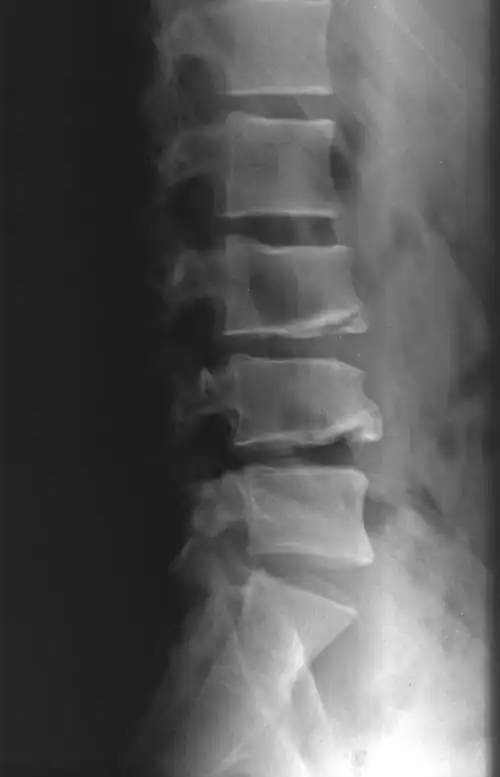

典型案例二:男,48岁,腰椎间盘突出.